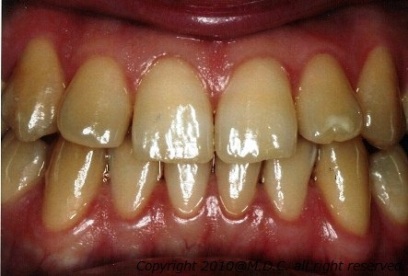

術前

術前の写真を見て判るように、もともとの歯には縞があります。ホワイトニングをしても濃い茶色の部分はあまり白くならず、薄茶色の部分のみ白くなったので縞が強調されてしまいました。